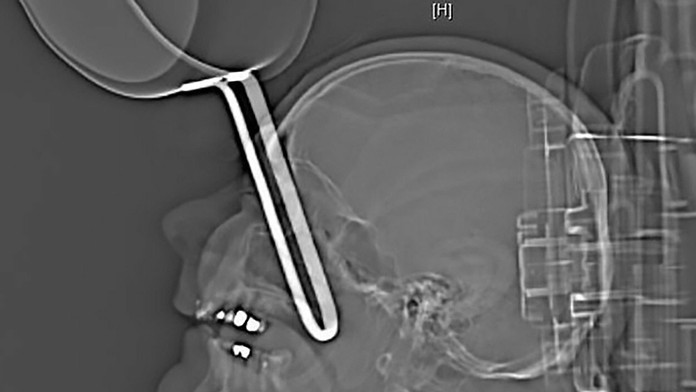

Nemec mal asi 10-centimetrovú časť panvice priamo v očnici. Poranený muž si stihol zavolať záchranku, ktorá ho v kritickom stave letecky prepravila do nemocnice.

Tam lekári spravili röntgenový snímok a neverili vlastným očiam. Muža museli ihneď operovať. Po niekoľkohodinovom zákroku sa ho podarilo zachrániť. Nemec im môže byť nesmierne vďačný, pretože mu zachránili aj zrak.

Rukoväť panvice mu minula mozog a prešla do lebky pod očnou buľvou. Po siedmich dňoch muža prepustili z nemocnice domov, uviedli noviny.cz.